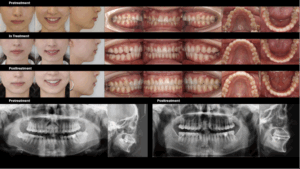

Caso práctico: Resultados funcionales en tiempo reducido

Plan de tratamiento convencional:

Extracción de piezas dentales (15, 25), inserción de minitornillos para anclaje, retracción de dientes anteriores superiores y distalización de molares, con una duración estimada de 30 a 36 meses.

Tratamiento de reposicionamiento mandibular con S8-SGTB:

Fase I: Avance mandibular a una relación incisal borde con borde mediante S8-SGTB.

Fase II: Extracción de dientes 38 y 48, distalización de molares menores con TAD y finalización con asentamiento oclusal.

⏱️ Duración total del tratamiento: 24 meses.

Resultados clínicos:

✅ Se evitaron las extracciones de premolares superiores.

✅ Se logró una rotación mandibular en sentido antihorario y una mejora de la morfología de ángulo alto a ángulo normal.

✅ Se mejoró el equilibrio facial y se redujo la retrusión mandibular.

✅ Alivio del chasquido y la presión articular en la ATM.

✅ Reducción de la duración total del tratamiento.